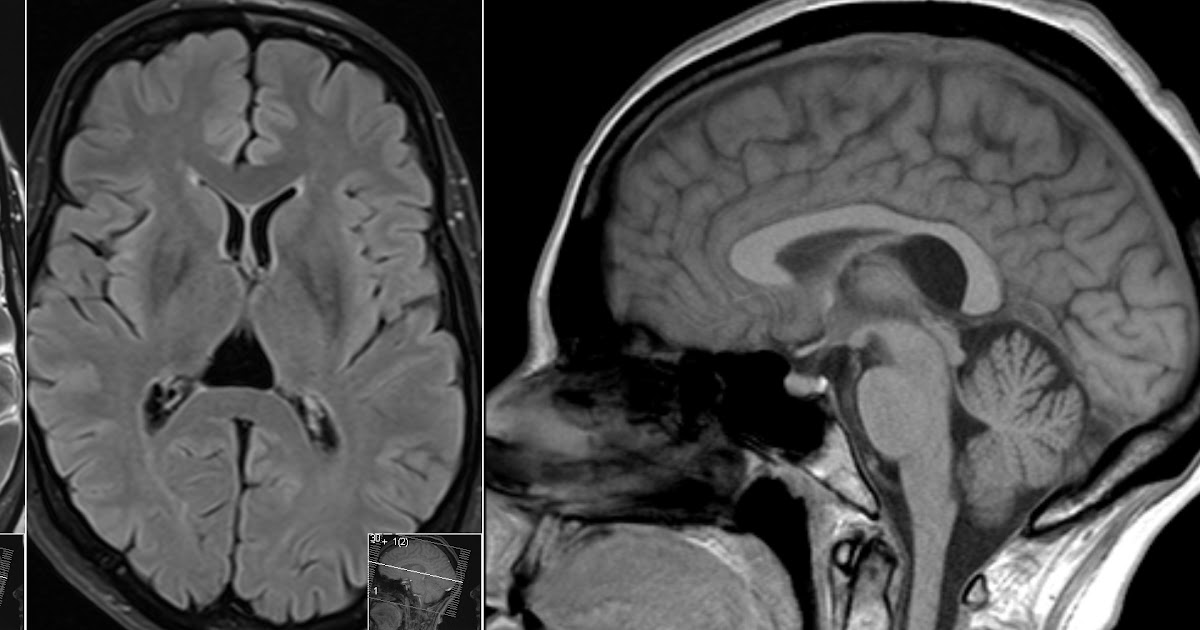

Figure 1 from Cavum velum interpositum cyst causing symptomatic trapped